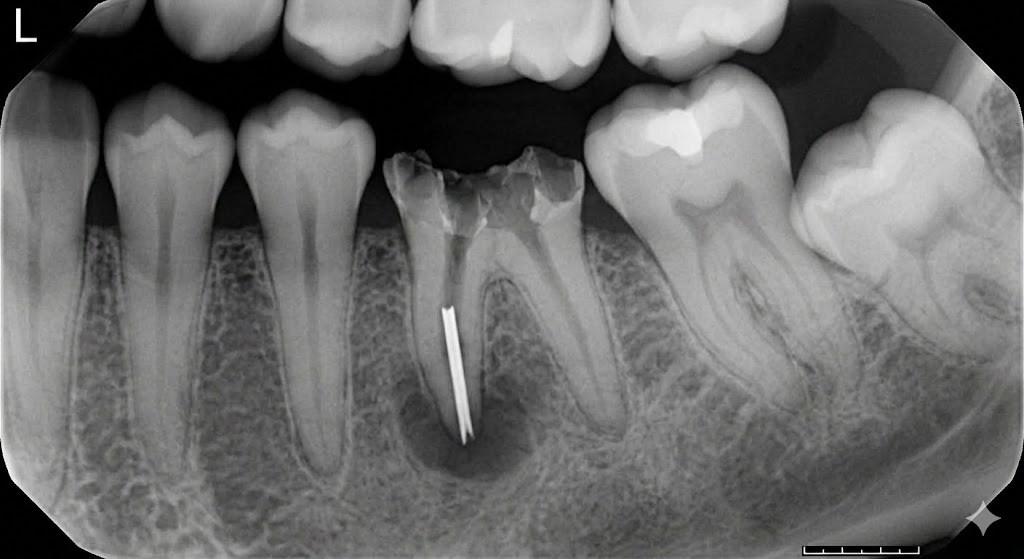

Це фундамент усього лікування. Лікар проводить прицільний рентген-знімок або, що краще, конусно-променеву комп'ютерну томографію (КТ) у 3D-проекції. Це дозволяє точно визначити:

- Довжину та тип уламка.

- Його глибину та положення відносно вигину каналу.

- Наявність запалення навколо кореня.

- Проводить візуальний та рентгенологічний контроль, щоб переконатися, що весь уламок видалений.